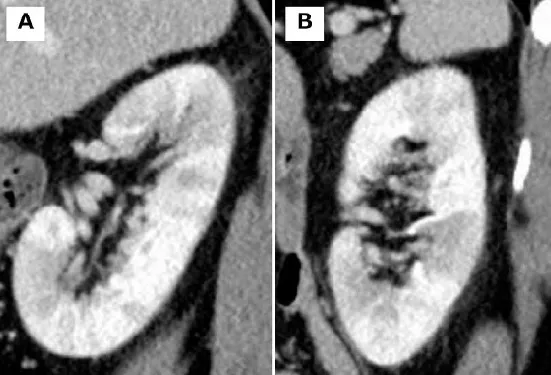

Uma causa incomum de hematúria glomerular intermitente!

Hematúria pós infecção, caso clínicos para auxiliar no entendimento de causas glomerulares comuns e raras...